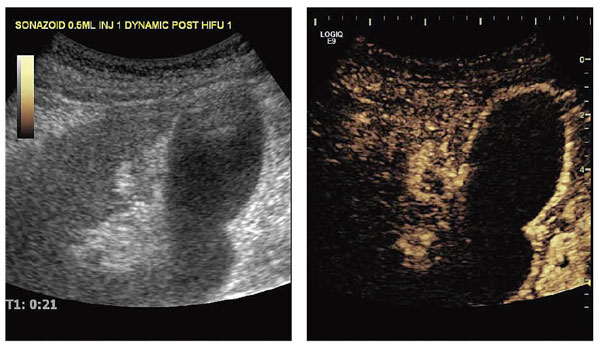

症例1(図2)は,約5cmの比較的大きな肝細胞がん(HCC)で,寝台を3mmピッチで動かしながら,腫瘍全体を焼灼した。HIFU治療は病変の大きさにより,1〜3日に分割して治療する。その日の焼灼の評価および翌日の焼灼予定範囲をより正確に確認するために,HIFU治療後,ソナゾイド造影超音波を施行する。Kupffer image(図2 b)では,焼灼領域がdefect像として描出されるほか,vascular imageでは残存血流の有無を確認することができる。治療後の評価はCTで行うことも可能だが(図2 c,d),造影超音波を用いれば,治療から効果判定までを超音波だけですませることが可能となる。

図2 症例1:約5cmの比較的大きなHCC

a:HIFU治療前の超音波画像

b:HIFU治療後のソナゾイド造影超音波画像(Kupffer image)